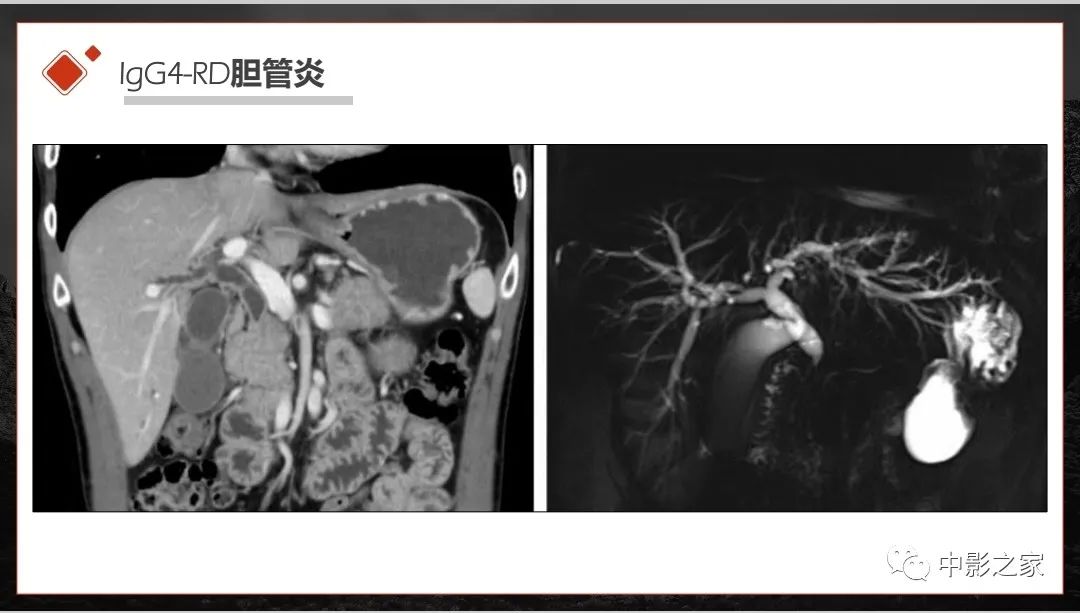

肾脏IgG4-RD临床、病理及影像特征